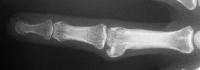

Case 1. 14 year old boy with radial prominence and ulnar deviation of the middle finger proximal interphalangeal joint. Painless, no history of trauma.

Radiographs showing well circumscribed calcification at the  proximal phalanx collateral ligament origin, 10 degrees of lateral angulation.